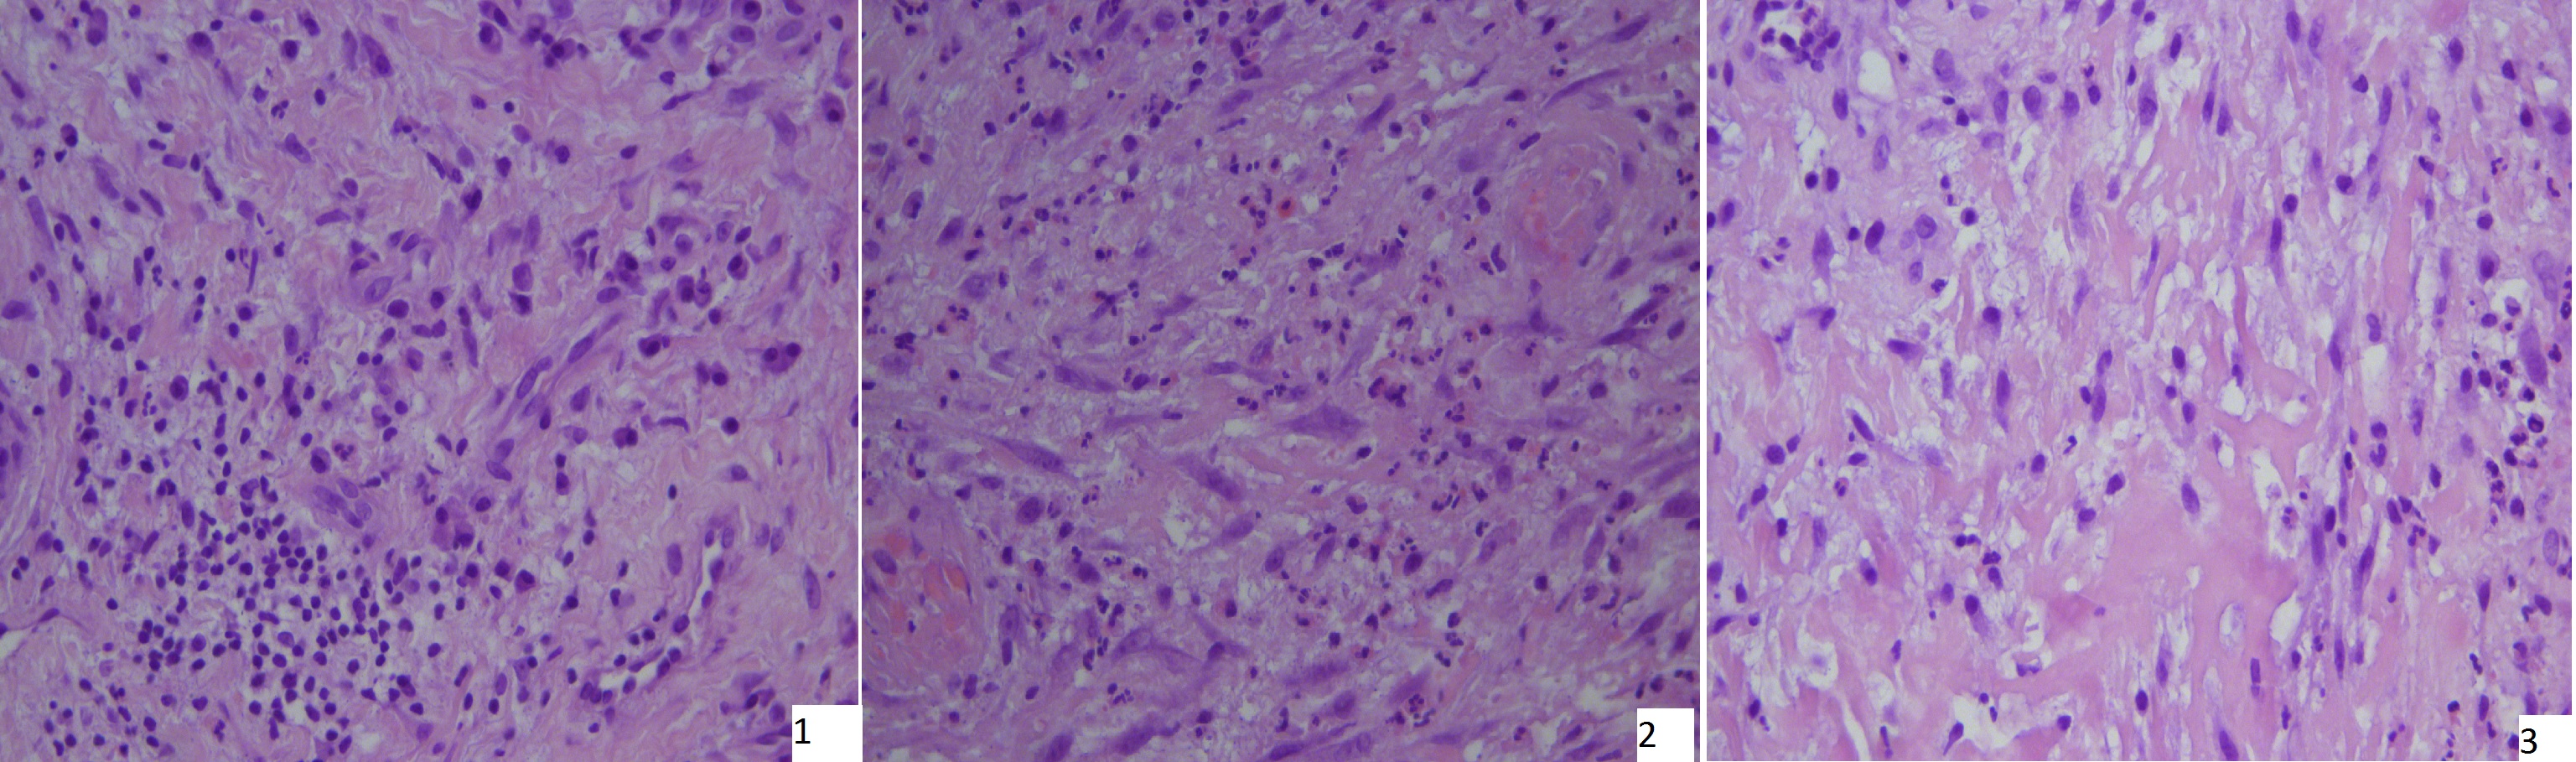

В ходе исследования зарегистрировано клинически значимое уменьшение размера раневых дефектов на 8,8±7% через 10 дней местного лечения и на 18,3±8% через 15 дней после начала местного лечения. Согласно данным гистологического исследования биоптатов ран, через 10 дней у всех больных определялся переход раны из фазы воспаления в фазу пролиферации: отмечалась тенденция к уменьшению воспалительного инфильтрата, к нарастанию количества фибробластоподобных клеток, фиксировалось наличие созревающей грануляционной ткани и появление формирующихся волокон соединительной ткани. Через 15 дней местного лечения в ранах всех включенных в исследование больных отмечено формирование зрелой грануляционной ткани, однако сохранялось наличие клеток воспалительного инфильтрата (смешанная лимфо- и лейкоцитарная инфильтрация). Типичная гистологическая картина биоптатов ран пациентов, включенных в исследование, представлена на рис. 1. Таким образом, несмотря на удовлетворительный гликемический контроль, отсутствие признаков инфекции по данным клинической картины, соблюдение условий разгрузки пораженной конечности и ежедневные перевязки ран, во всех ранах имеются признаки воспаления, что может говорить о нарушении репаративных процессов в ране. Полученные данные согласуются с результатами исследований Комелягиной Е.Ю. с соавт., где были зафиксированы наличие неполной репарации и склонность к фиброзу у пациентов с нейропатической формой СДС длительностью более года [13], а также с результатами зарубежных исследователей, где были зафиксированы увеличение количества фибробластов и сохранение полиморфноядерных лейкоцитов на 3-и сутки местного лечения у лабораторных моделей [7].

Рис. 1. Типичная гистологическая картина биоптатов раны на 0, 10, 15-е сутки местного лечения: 1) Эпидермис сохранен, в дерме очаги плазмоцитарной и лимфоцитарной инфильтрации; 2) Созревающая грануляционная ткань представлена мелкими сосудами, диффузной лимфо- и лейкоцитарной инфильтрацией (сегментоядерные нейтрофилы) и нежной рыхлой соединительной тканью; 3) Зрелая грануляционная ткань, умеренная лимфоцитарная инфильтрация и лейкоцитарная инфильтрация, представленная плазмоцитами с преобладанием сегментоядерных нейтрофилов, выраженная пролиферация фибробластов, сосудистый лейкостаз.